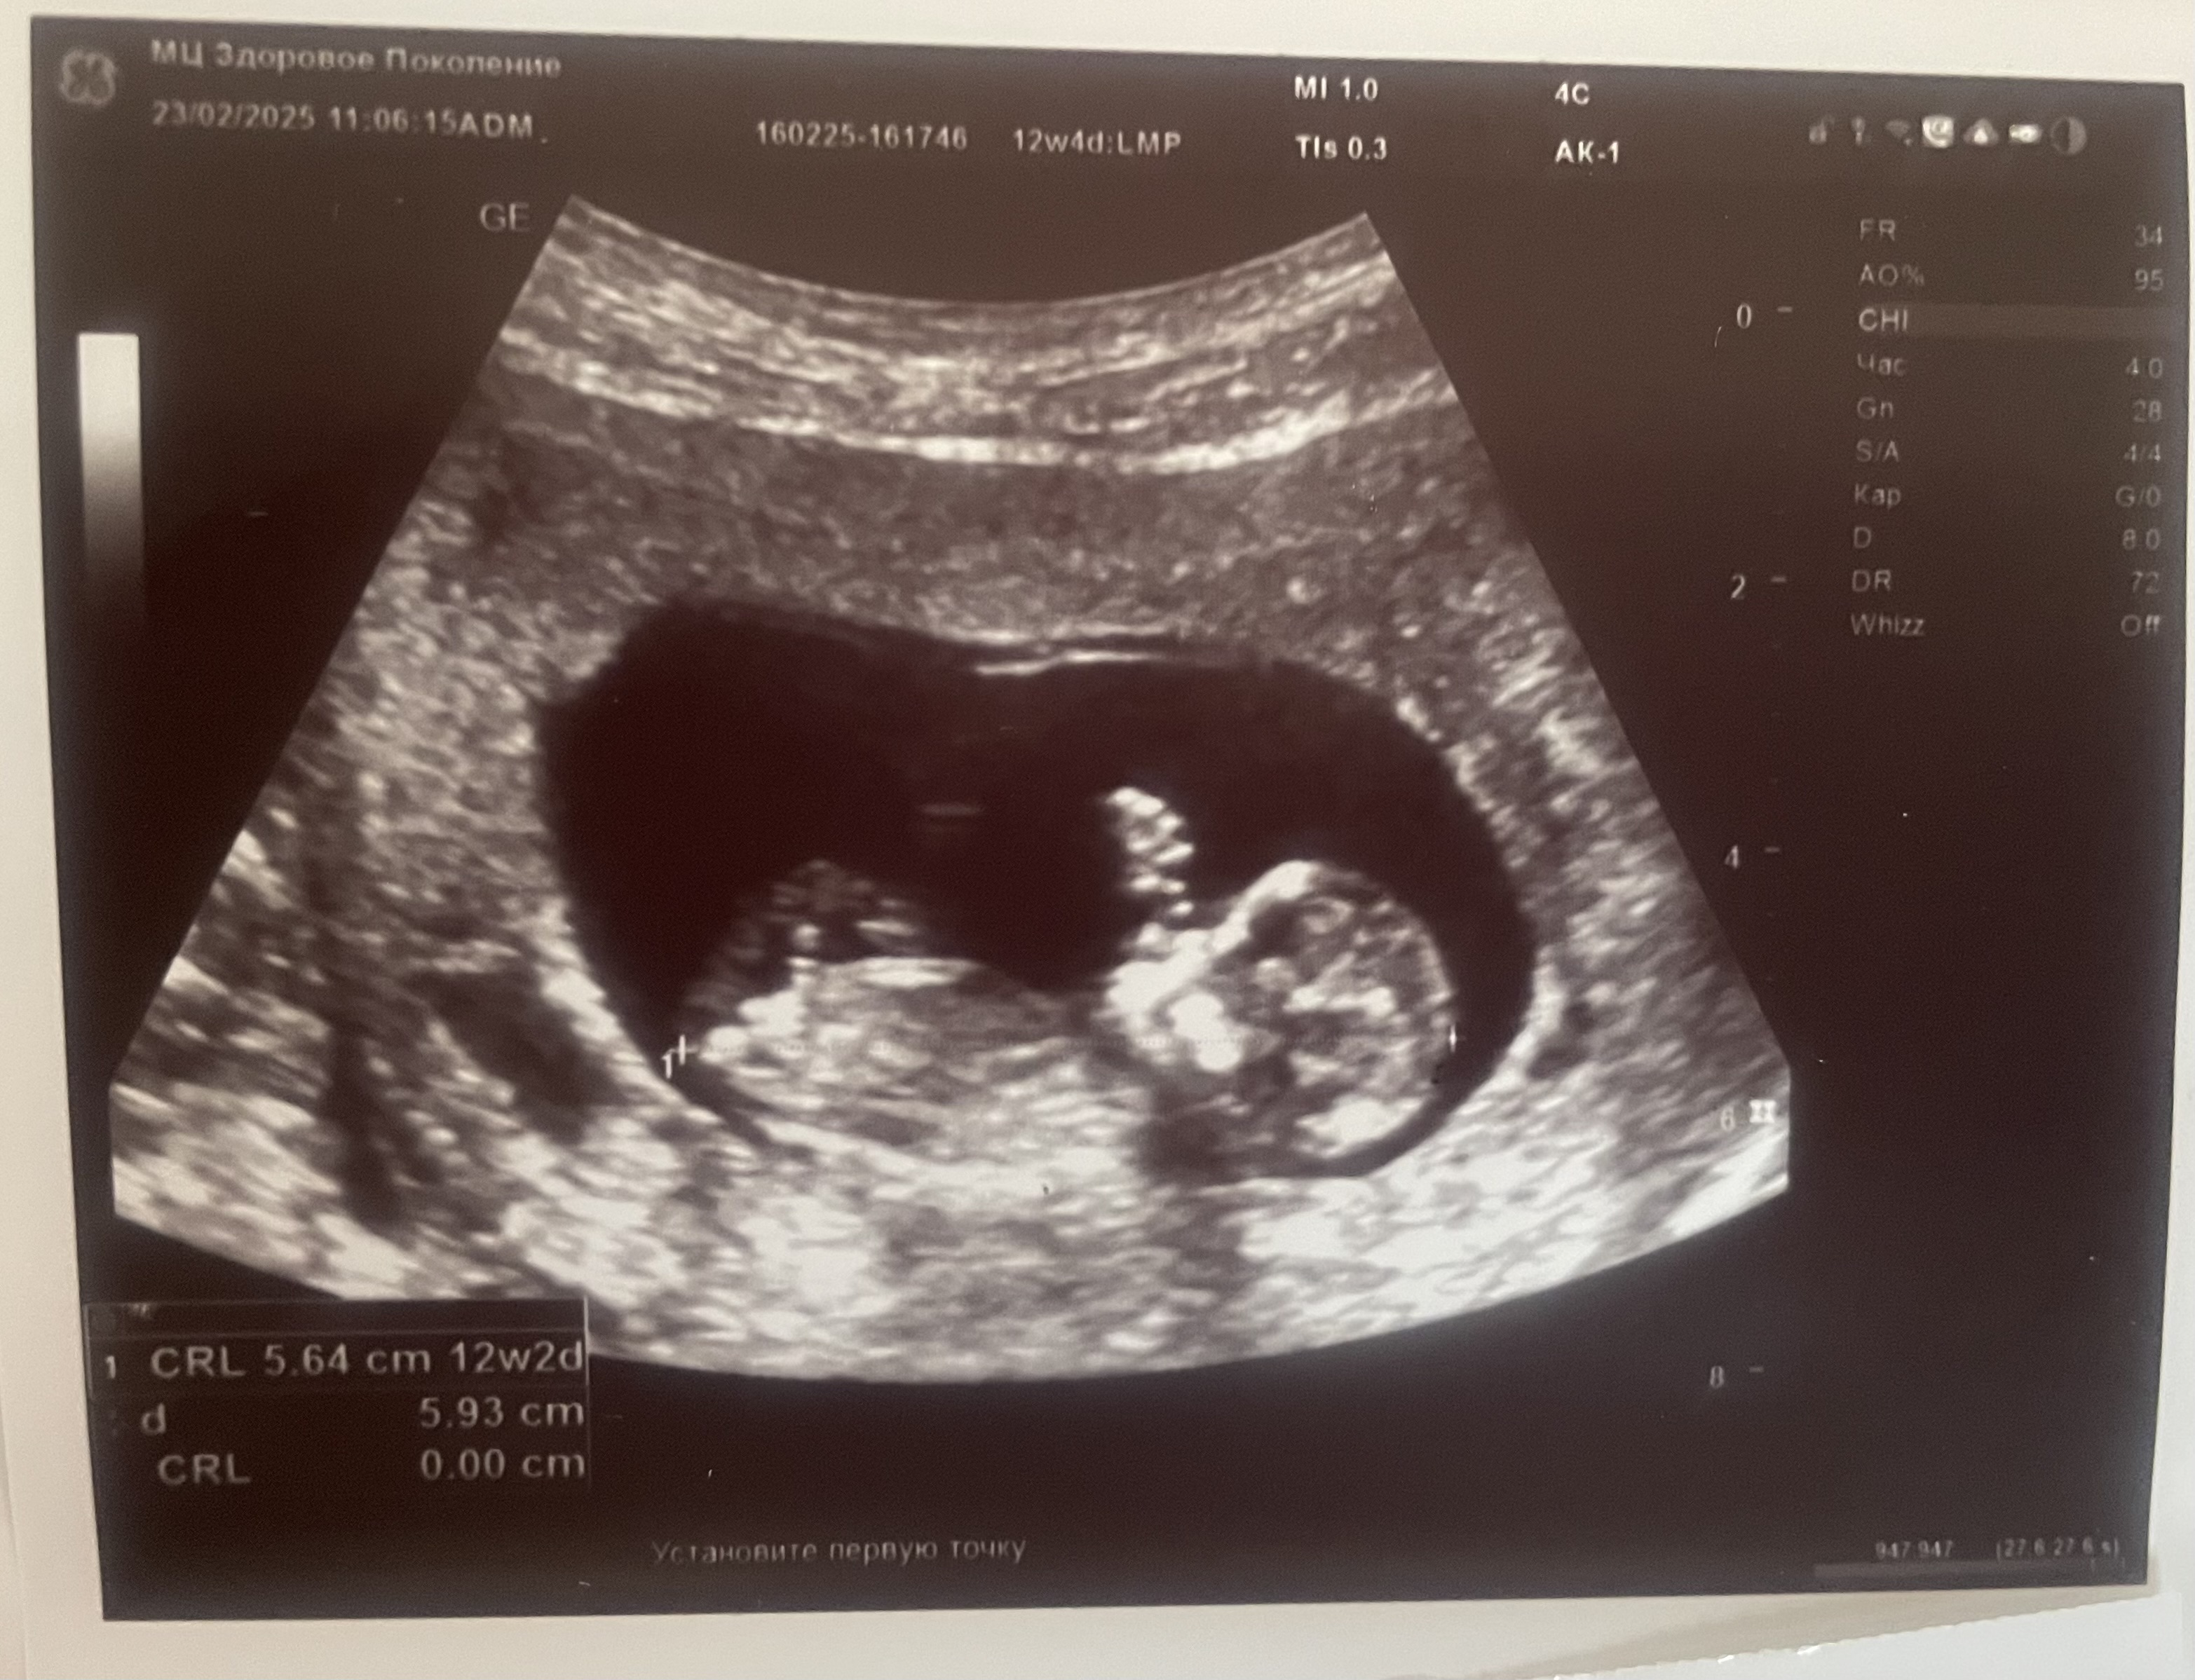

Мальчик или девочка?)

Девчуля, ну очень похоже по бугорку🥰

Девочка.

Lena Sorokina, тут качество снимка хуже и менее понятно. А на фото в посте половой бугорок расположен вдоль позвоночника, это признак девочки. У дочки на первом скрининге точно так же было. У мальчиков на этом сроке бугорок вверх под углом торчит.